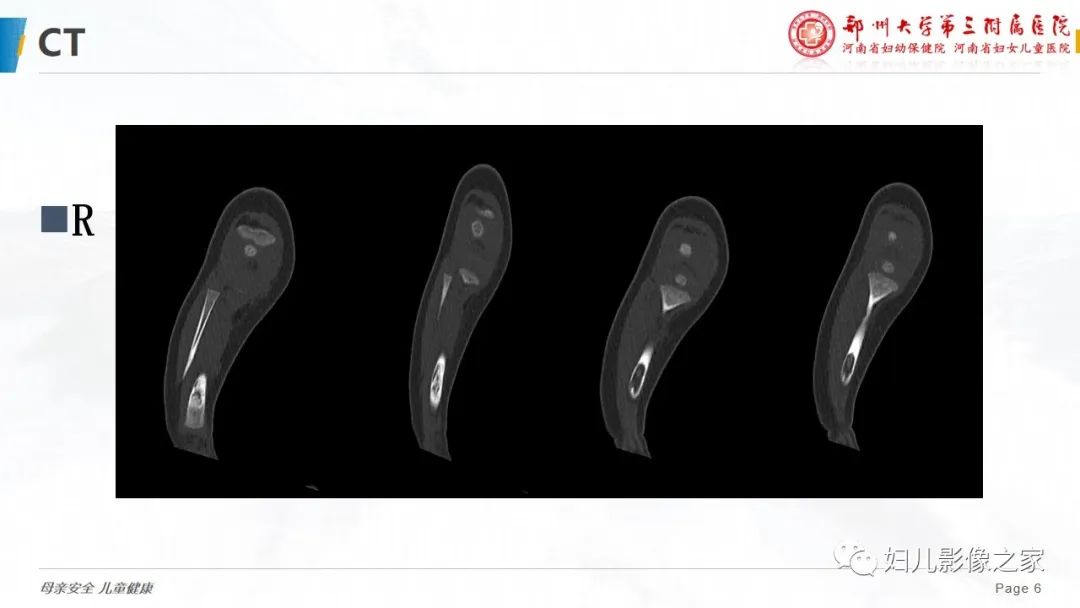

【PPT】骨纤维结构不良-6